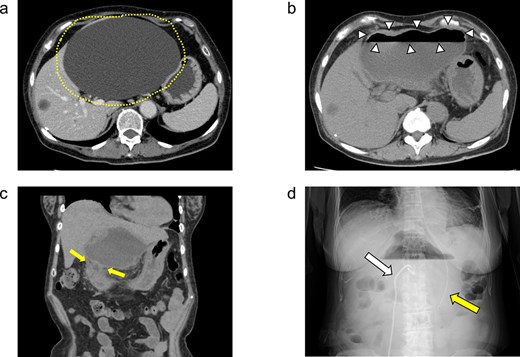

Because the hepatic cyst showed chronic inflammation and did not disappear, on day 42, the surgery was performed laparoscopically for the infected hepatic cyst (Fig. 3a). The cyst wall was opened, and a large amount of purulent fluid was discharged (Fig. 3b). Hepatic-cyst deroofing was performed (Fig. 3c–e). A depression was found in the lumen of the fenestrated cyst near the duodenal bulb, which was thought to be the penetration site between the hepatic cyst and the duodenum (Fig. 3f), and the depression was closed (Fig. 3g). One closed drain was placed at the site of the fenestrated hepatic cyst (Fig. 3h). The histopathological examination revealed no evidence of malignancy of the cyst wall.

(a–h) Operative findings during the patient’s laparoscopic surgery. (a) Inflammatory tissue adhesions were observed on the peritoneum, omentum, and hepatic cyst. (b) A large amount of purulent fluid was discharged from the opened hepatic cyst. (c, d) The hepatic cyst wall was resected at the junction of the hepatic cyst and the liver parenchyma using the LigaSure™ vessel sealing system (Medtronic, Dublin, Ireland). (e) The laparoscopic hepatic cyst deroofing was completed. (f) A depression in the lumen of the fenestrated cyst near the duodenal bulb was observed, which was thought to be the penetration site between the hepatic cyst and the duodenum. Arrowheads: The depression in the lumen of the fenestrated cyst near the duodenal bulb. (g) The depression was closed using a 3–0 Vicryl® suture (Ethicon, Cornelia, GA, USA). (h) After the peritoneal lavage, one closed drain was placed at the site of the fenestrated hepatic cyst.